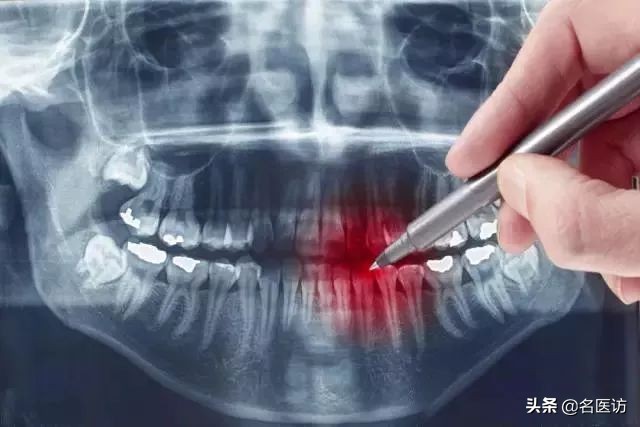

2、拍片

拍X光牙齿及头部骨头照片。目的是为了看你的牙齿及骨骼发展方向等,以利于以后制定准确的矫正方法。